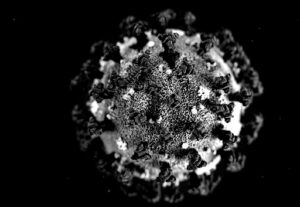

سوس ماسة : الوضع الوبائي يقارب تسجيل 13 ألف حالة نشطة بالجهة، و هذه تفاصيل الحالة الوبائية بعمالات و أقاليم الجهة:

دراسة أمريكية : المصابون السابقون غير الملقحين ضد كورونا أكثر عرضة لخطر الإصابة مجددا

خبير يتحدث لجريدة أكادير24 عن المتحور اوميكا

كورونا سوس ماسة تضع الجهة في الرتبة الثانية وطنيا من حيث الوفيات، و رقم كبير من الإصابات يسجل في أغلب مدن الجهة .